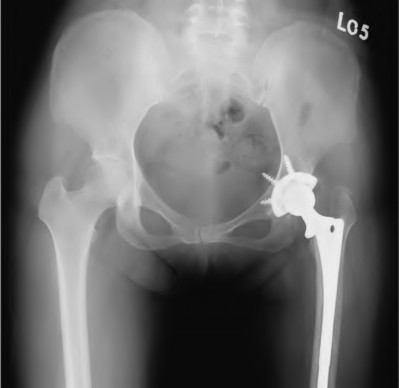

An 82-year-old woman falls and sustains the fracture shown in figure A. She denies any history of dislocation or prodromal pain prior to her fall. What is the most appropriate treatment?

The radiograph demonstrates a periprosthetic femur fracture extending to the tip of the stem. The long spiral fracture is consistent with a loose implant. The bone stock is sufficient. Therefore, this fracture pattern would classify as a B2 using the Vancouver classification system. The Vancouver classification for periprosthetic femoral fractures is simple yet incorporates all the pertinent factors such a location, stem fixation, and bone stock. Type A is a trochanteric fracture- lesser or greater. These can be treated non-operatively usually and ORIF if symptomatic. Type B fractures are around or just below the stem and are subdivided into three types. Type B1 is a fracture with a well fixed stem.

The treatment is cable plating or allograft struts or a combination of the two. Type B2 is a fracture with a loose stem with good bone stock. The treatment is a cementless porous coated long stem atleast two diameter length past the

fracture site. Type B3 is a fracture with a loose stem and comminution. For younger patients, use cementless porous coated long stems with allograft struts. For older patients, consider a tumor prosthesis. Cement fixation is sometimes necessary Type C is a fracture well below the stem tip. These can be treated independently of the prosthesis.

Springer et al showed optimal outcomes with revision involving long extensively-coated femoral stems for Vancouver B fractures.

Masri et al review the classification and treatment of periprosthetic femur fractures.

Figure A shows a lytic lesion of the proximal femur with an intramedullary implant. Figure B shows a proximal femoral replacement.